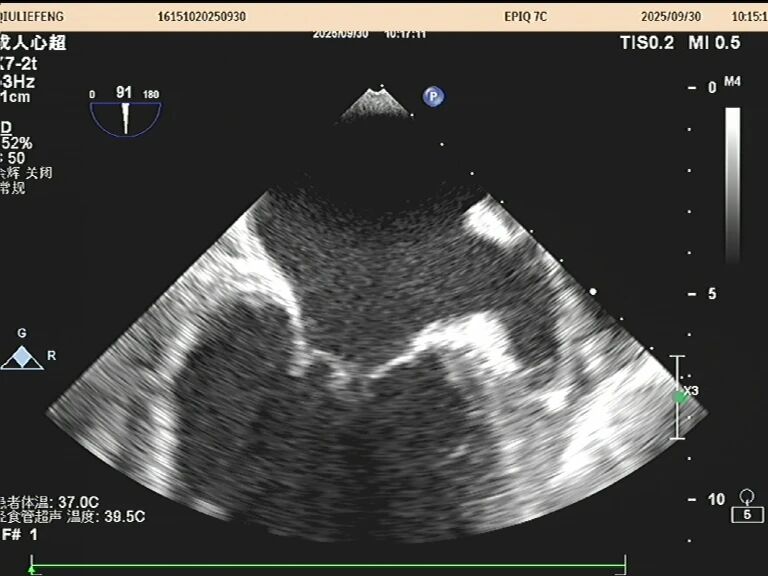

于是,一根如面条般柔软、顶端带着微型摄像头的探头,会从您的口腔缓缓进入食道。这个位置堪称完美,探头能紧贴着心脏,利用超声波为其拍摄一场无死角、超高清的“内部直播”。以前藏在背后的细微结构比如心耳里是否藏有血栓、人工瓣膜是否严丝合缝、心脏瓣膜上的小赘生物,此刻都一览无余。

这场大约15-20分钟的“心脏之旅”,价值巨大。它是诊断许多复杂心脏问题的“金标准”,如同为医生点亮了一盏明亮的探照灯,直击病灶。无论是指导心脏手术、排查脑卒中元凶,还是评估重症患者的心脏功能,它都提供了最关键的依据。